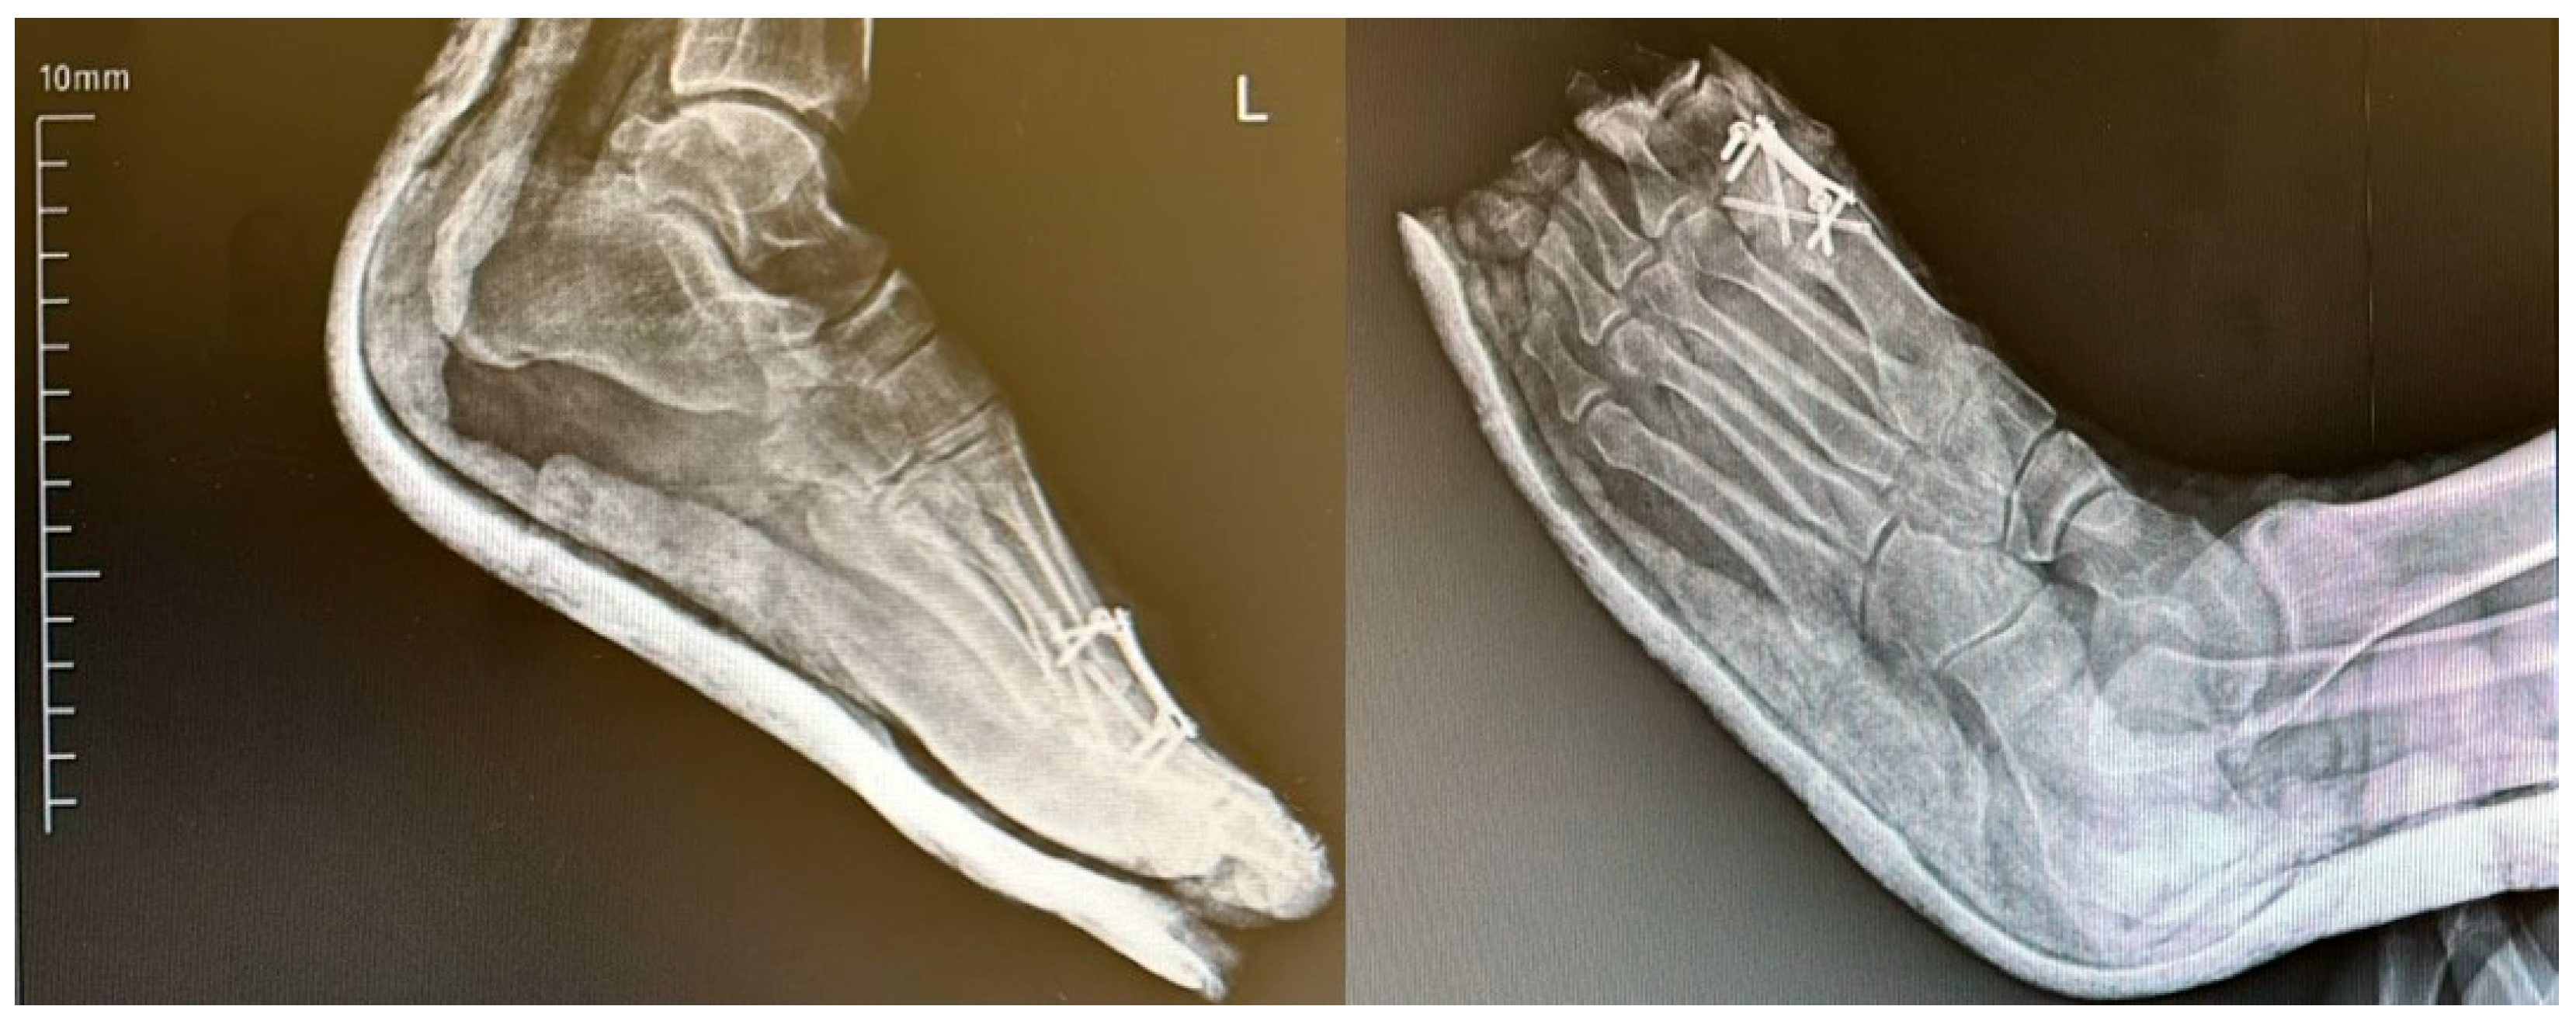

While dorsiflexion angles in Group 2 remained within the accepted normal range (15.9–26.9°), the values were significantly lower compared to Group 1, where angles exceeded the average upper limit. This difference was statistically significant (p = 0.04) (Figure 6).

A lateral radiographic view demonstrating the arthrodesis angle is shown in Figure 6. The image illustrates proper alignment of the first toe with approximately 10–15° of dorsiflexion, which is considered the ideal postoperative fusion position for restoring gait mechanics and ensuring optimal functional outcomes (Figure 7).

Figure 6. Representative postoperative radiographs of patients from each fixation group. Group 1: Dorsal locking plate fixation. Group 2: Crossed cortical screw fixation. Group 3: Combination of dorsal plate and crossed screws. L: Left.